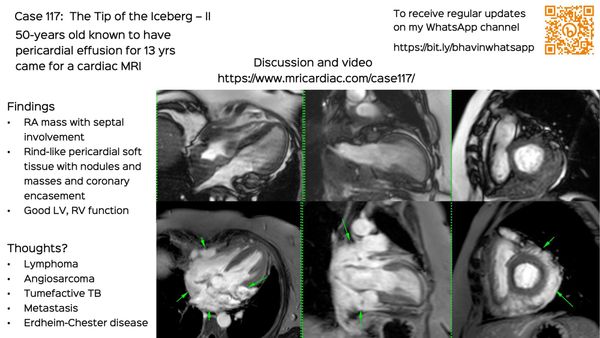

A snippet on tumors that need a biopsy or either the tumor itself or of a related lesion for diagnosis.

Sometimes, the heart is just one of the organs involved and a cardiac MRI or CT can start a cascade leading to the final diagnosis.